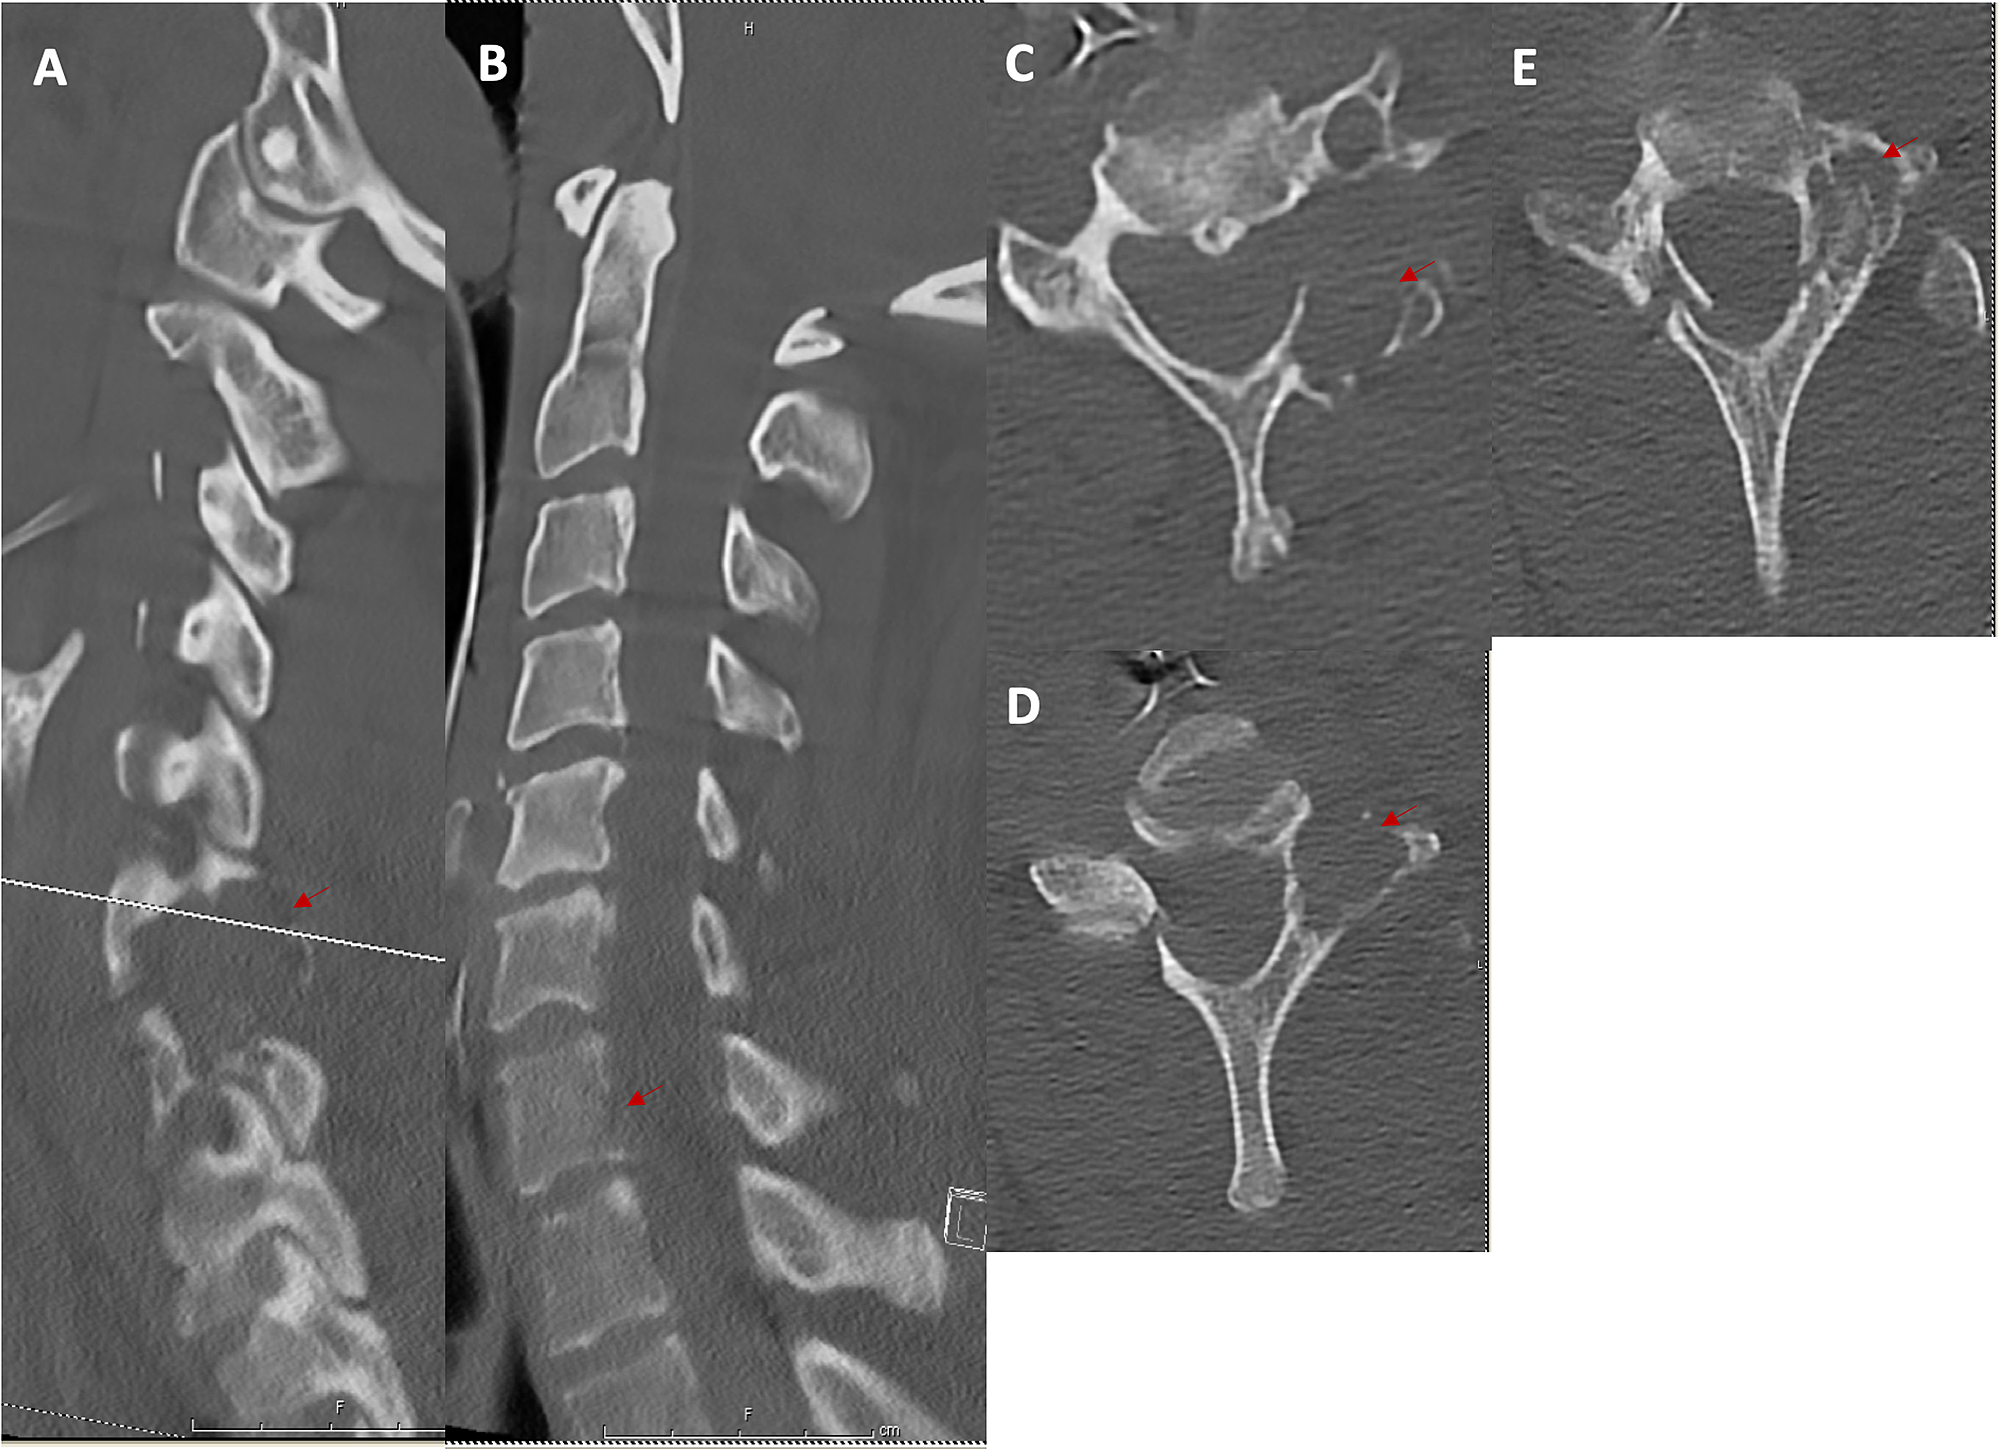

Cureus Tenosynovial Giant Cell Tumor of the Cervical Spine Case

From www.cureus.com

Cureus Tenosynovial Giant Cell Tumor of the Cervical Spine Case Facet Joint Giant Cell Tumor facet joint neoplasms like osteoid osteoma, plasmacytoma, tenosynovial giant cell tumor, and osteochondroma are best. osteolytic bone destruction in the area of the facet joint with a soft tissue mass and hypointensity on t2wi images. Differentiate between giant cell tumor and other bone lesions through a comprehensive analysis. We describe fdg pet/ct findings in a. facet joint. Facet Joint Giant Cell Tumor.

Cureus Tenosynovial Giant Cell Tumor of the Cervical Spine Case Facet Joint Giant Cell Tumor facet joint neoplasms like osteoid osteoma, plasmacytoma, tenosynovial giant cell tumor, and osteochondroma are best. facet joint neoplasms like osteoid osteoma, plasmacytoma, tenosynovial giant cell tumor, and. facet joint neoplasms like osteoid osteoma, plasmacytoma, tenosynovial giant cell tumor, and osteochondroma are best. Differentiate between giant cell tumor and other bone lesions through a comprehensive analysis. facet. Facet Joint Giant Cell Tumor.